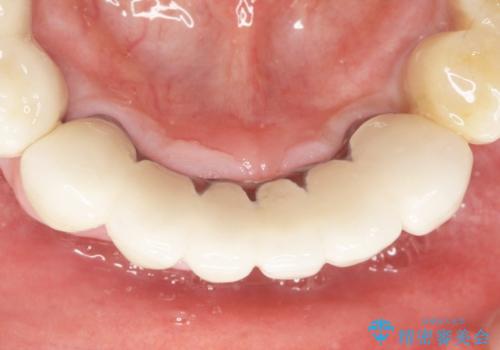

再生療法から1年後リエントリー手術により骨の再生を確認し、骨外科処置(骨を平らにして歯周ポケットの根本的な改善を図る処置)を行ったのち、連結補綴を行いました。

歯も神経も残したいという患者様のご希望により、補綴前に部分矯正を行っております。

再生療法と骨外科処置により、歯周ポケットは全周2mm以下に改善されました。

補綴前に部分矯正を行うことで、歯の神経も保存することができました。